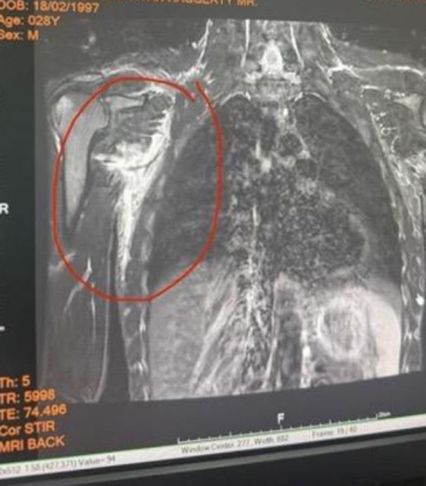

“แต่โชคร้าย เมื่อ 3 สัปดาห์ก่อน ผมได้รับบาดเจ็บที่มือซ้าย ต้องเย็บถึง 8 เข็ม ตอนนั้นผมคิดว่าเป็นแค่เรื่องเล็ก ๆ ที่จะผ่านไปได้ จึงตัดสินใจซ้อมต่อ ทีมงานช่วยผลักดันผมอย่างเต็มที่เพื่อให้ฟิตทันขึ้นชก แต่สัปดาห์ถัดมา ผมเกิดบาดเจ็บซ้ำ เอ็นหัวไหล่ฉีกจนลามไปถึงกล้ามเนื้อหลัง ซึ่งเกิดขึ้นระหว่างซ้อม ตอนออกหมัดแรกผมก็รู้แล้วว่ามันผิดปกติ จึงรีบไปตรวจด้วยคลื่นแม่เหล็กไฟฟ้า (MRI) และผลก็ยืนยันว่า ผมไม่สามารถขึ้นชกไฟต์นี้ได้”